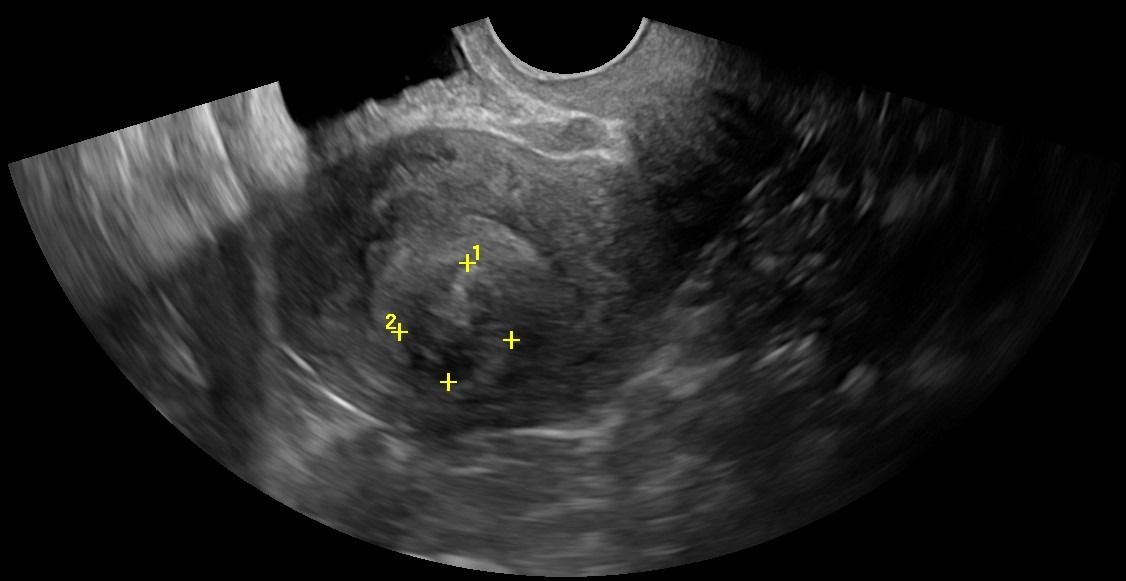

- Μήτρα: Με το Διακολπικό Υπερηχογράφημα, μπορεί να αξιολογηθεί το μυομήτριο και να εντοπιστεί η παρουσία ινομυωμάτων. Το πάχος του ενδομητρίου μπορεί να μετρηθεί με ακρίβεια, κάτι που είναι κρίσιμο τόσο για γυναίκες αναπαραγωγικής ηλικίας όσο και για γυναίκες μετά την εμμηνόπαυση ή μετά από θεραπευτικά σχήματα για νεοπλάσματα.

- Ωοθήκες: Η απεικόνιση των ωοθηκών περιλαμβάνει την αξιολόγηση του μεγέθους, της μορφολογίας και της υφής τους. Με το Διακολπικό Υπερηχογράφημα, μπορούν να μετρηθούν τα ωοθυλάκια και να διερευνηθεί η παρουσία συνδρόμου πολυκυστικών ωοθηκών. Οι εστιακές βλάβες στις ωοθήκες, συμπαγείς ή κυστικές, μπορούν να αξιολογηθούν ως καλοήθεις ή ύποπτες, με τη βοήθεια του Έγχρωμου Doppler για την απεικόνιση της αγγείωσης και της ροής του αίματος.